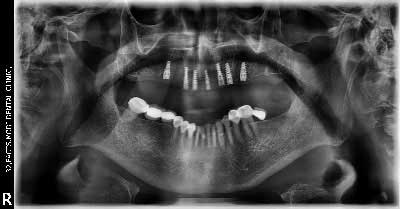

(10) Dental Implant - Full Mouth

Before Treatment

After Treatment

Patient came with a problem in chewing food and multiple loose teeth in upper and lower jaw and was interested in getting a whole new set of teeth in both the jaws. So after removal of all the weakened teeth and placement of multiple implants, he was given implant supported bridge.